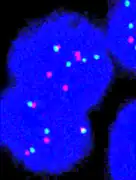

FISH can be used to measure the number of copies of the gene which are present and is thought to be more reliable than immunohistochemistry.[47] It usually uses chromosome enumeration probe 17 (CEP17) to count the amount of chromosomes. Hence, the HER2/CEP17 ratio reflects any amplification of HER2 as compared to the number of chromosomes. The signals of 20 cells are usually counted.

-

This cell displays 2 signals of HER2 (red) and 3 signals of CEP17 (green) -

Two signals that are closer to each other than the signal diameter count as one. -

One of these signals is too faint, and is presumably debris. -

Cells with only one type of signal are excluded from the count. -

Overlapping cells are also excluded from the count. -

A yellow signal counts as one red and one green (which are overlapping)